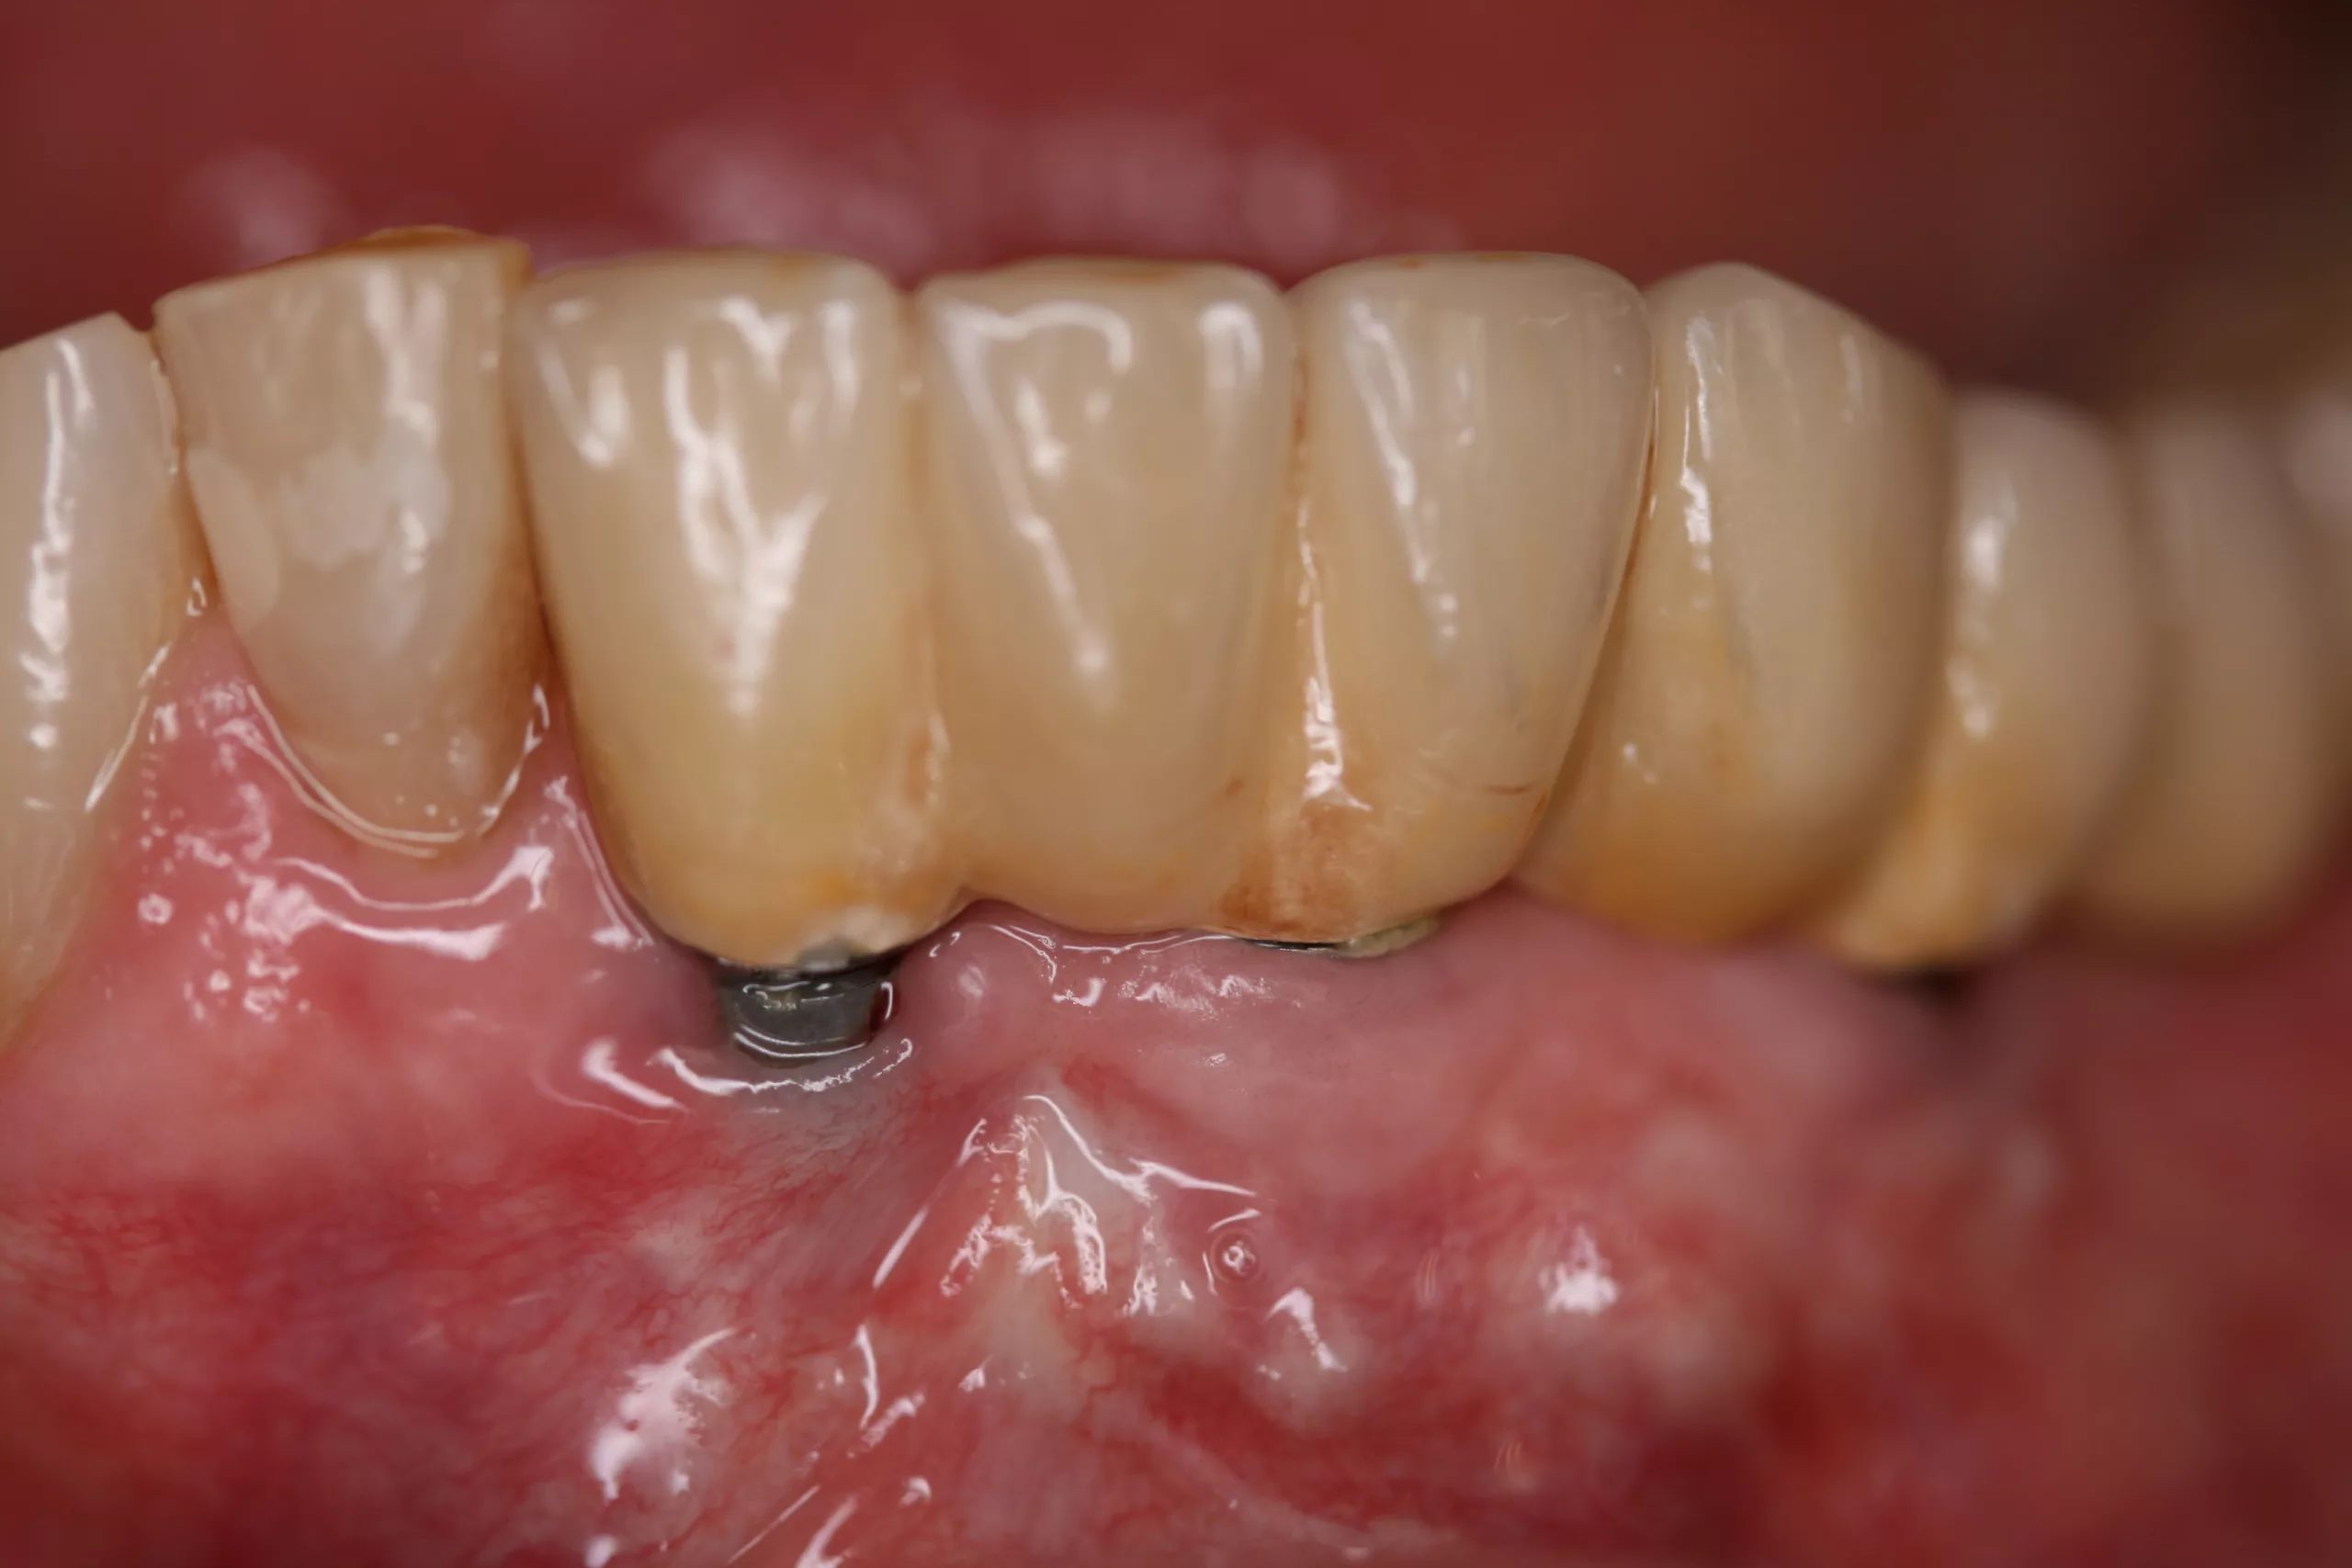

Zum Timing der Nachsorge von Implantaten existieren keine systematischen Langzeitstudien vergleichbar denen bei Zähnen. Es ist jedoch bekannt, dass Mukositis und Periimplantitis häufig auftreten. So stellte eine umfangreiche systematische Reviewstudie und Metaanalyse bei 63% der Implantatpatienten Mukositis fest, von der mehr als 30% der Implantate betroffen waren. Nahezu 20% der Patienten litten an einer Periimplantitis, von der ca. 10% der Implantate betroffen waren [13]. Zudem schreitet der Knochenabbau bei Periimplantitis meist rascher fort als bei Parodontitis. Deshalb sollte die Häufigkeit der Implantatnachsorge mindestens der von Zähnen entsprechen. Das bedeutet: Wenn ein Implantat einen Zahn ersetzt, der aufgrund von schwerer Parodontitis verloren ging, sollte das Recallintervall 3 Monate betragen. Falls die Implantation aus nichtparodontalen Gründen erfolgte, reicht wohl ein Termin alle 4 (bis maximal 6) Monate aus. Beim Timing der Nachsorge sind lokale und systemische Risikofaktoren zu berücksichtigen [13]. Bei Rauchern beispielsweise treten Mukositis und Periimplantitis deutlich häufiger auf als bei Nichtrauchern [14].